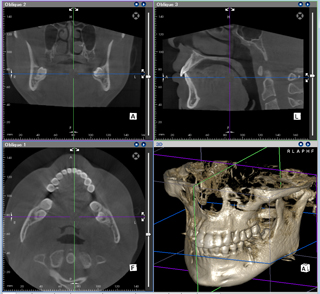

「まずは 必ずCT撮影を 行っているか?」 これです。

CT写真からは 通常の2次元の情報からは 絶対に知りえない 情報が正確に把握できます。

インプラント治療の 安心 安全 の ポイントはCTを撮影してくれるかどうかはまず第一段階です。